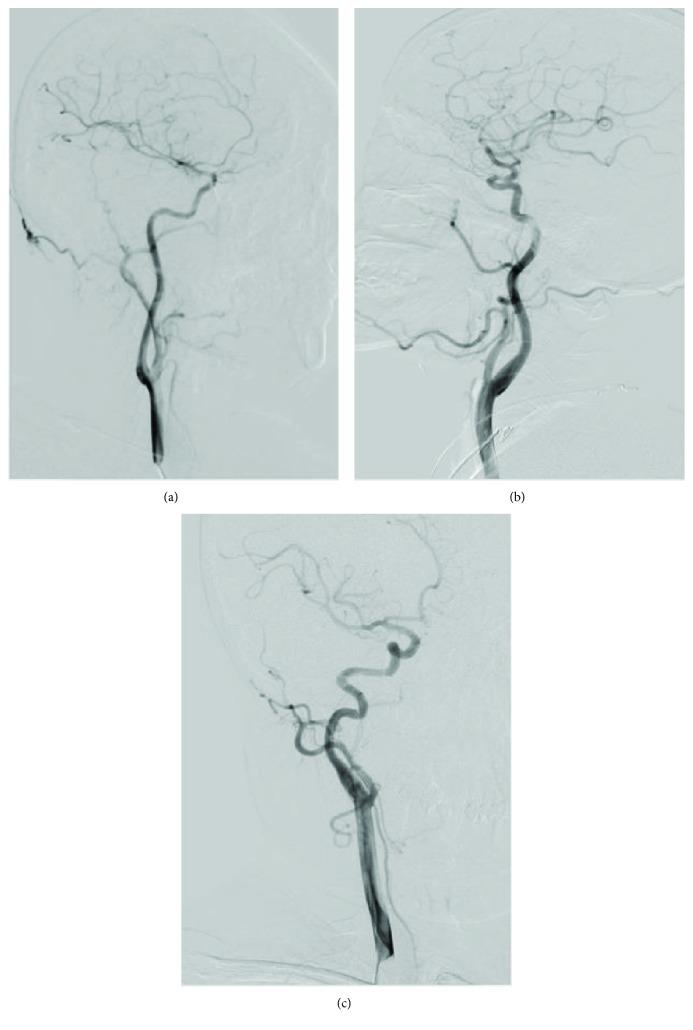

Hospitalized patients from March 2017 to October 2017 who underwent digital subtract angiography (DSA) were divided into non-CAMV group, T-type group, K-type group, and C-type group according to their carotid artery morphology. Cognitive function in each group was evaluated with the Mini-Mental State Scale (MMSE), the Montreal Cognitive Assessment (MoCA), the Verbal Fluency Test (VFT), and the Digital Span Test (DST).

A total of 96 patients were included in the study (32 in non-CAMV group, 34 in T-type group, 30 in K-type group, and none in C-group). The positive rate of MMSE in the non-CAMV group, the T-type group, and the K-type group was 15.6%, 14.7%, and 20.0%, respectively, with no statistical difference in the three groups ( = 0.836). The positive rate of MoCA in the K-type group was significantly higher than that in the non-CAMV and the T-type groups ( < 0.001), but there was no significant difference between the non-CAMV group and the T-type group ( = 0.826). The VFT, DST forward score, and backward score in the K-type group were significantly lower than those in the non-CAMV and the T-type groups ( < 0.001).